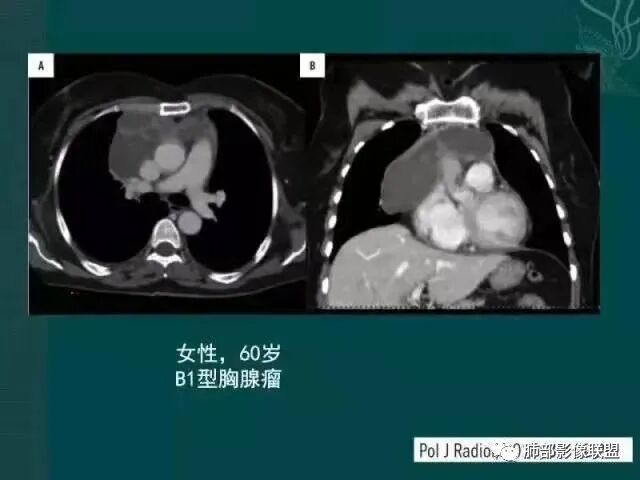

黄勇老师胸腺瘤总结

【每日晨读】胸腺瘤or胸腺癌,且听南边老师娓娓道来

胸腺瘤之罕见类型